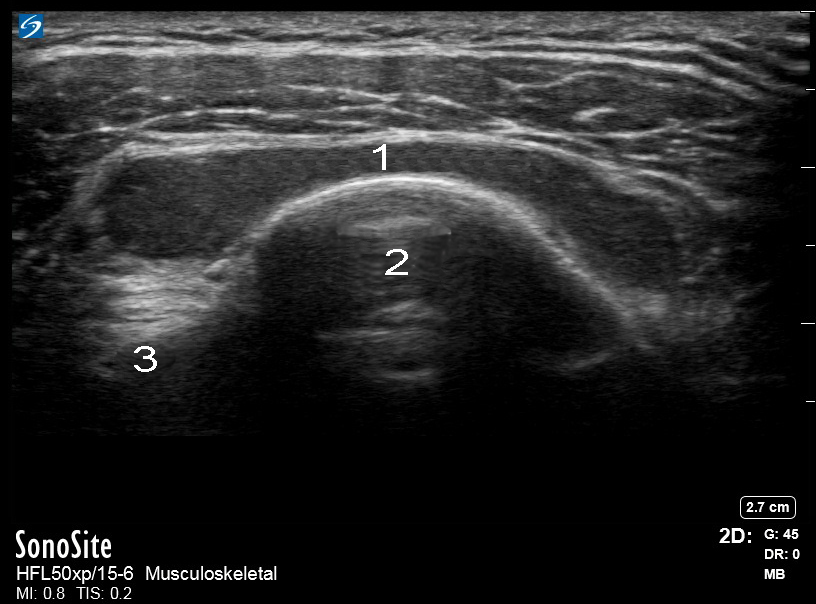

肩部横向肩峰下滑囊炎图像

肩部图像 - 肩袖的轴位和远端

肩峰下滑囊

大结节 (GT)

二头肌腱 (BT)